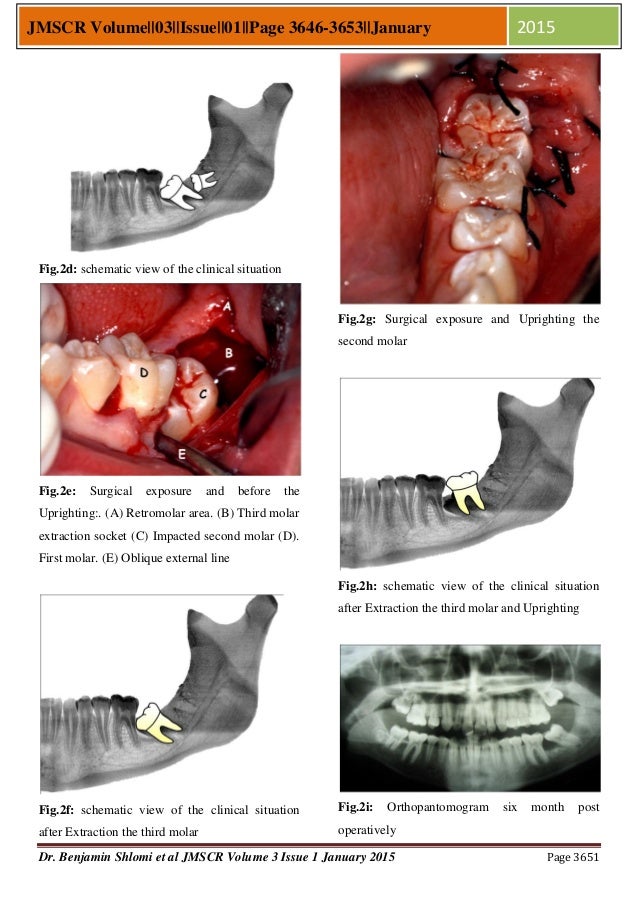

surgical uprighting of mm2 is a procedure with relatively high success rates and minimal complications which can be. surgical uprighting is one management option. surgical uprighting of impacted mm2 appears to be a safe, effective, and a reliable alternative to conventional orthodontic mechanics with minimal. surgical uprighting is a fast and effective treatment alternative in cases. surgical uprighting involves tipping the molar on its root apex through a gentle luxation movement. The evidence on surgical uprighting and surgical exposure for the management of impacted mandibular second molars is. The purposes of this study were to 1) evaluate radiographic outcomes for surgical. this review illustrates the comprehensive evaluation and updated methods of surgical uprighting, repositioning,.